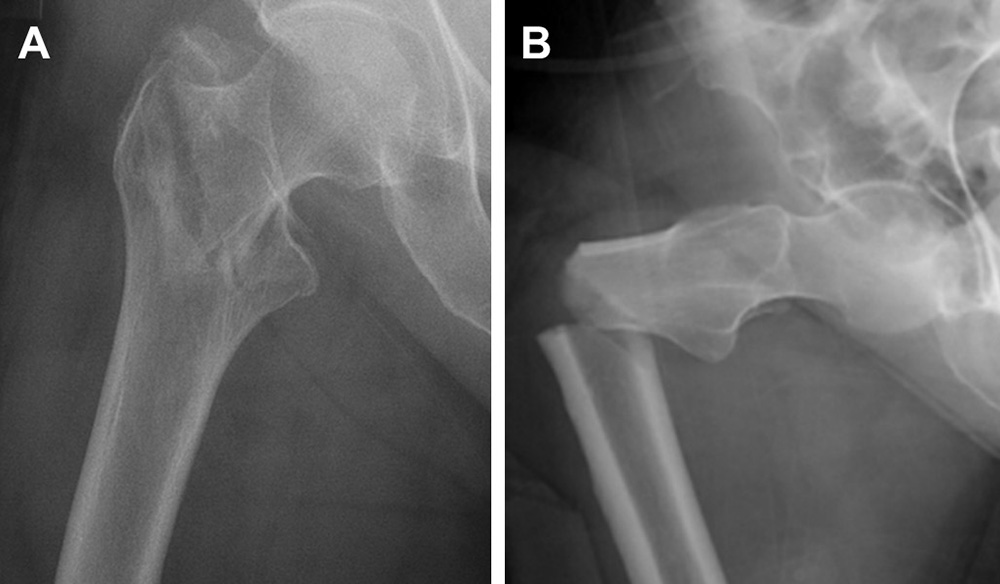

It’s been known for some time that prolonged use of bisphosphonates can put people at risk for atypical femoral fracture (AFF), a break in the shaft of the femur that can occur as a result of little or no trauma. The Donnelly group set out to understand the link between the drugs and AFF.

For this study, the team examined biopsies of cortical bone – the outer layer – from the shaft of the femur obtained from postmenopausal women during fracture repair surgery. Analysis of bone samples was conducted at the Cornell Center for Materials Research and with collaborating labs at Lawrence Berkeley National Laboratory and University Medical Center Hamburg-Eppendorf.

The participants were placed in five groups, based on fracture type and bisphosphonate use. Some of the women in the study had used bisphosphonates for more than eight years.